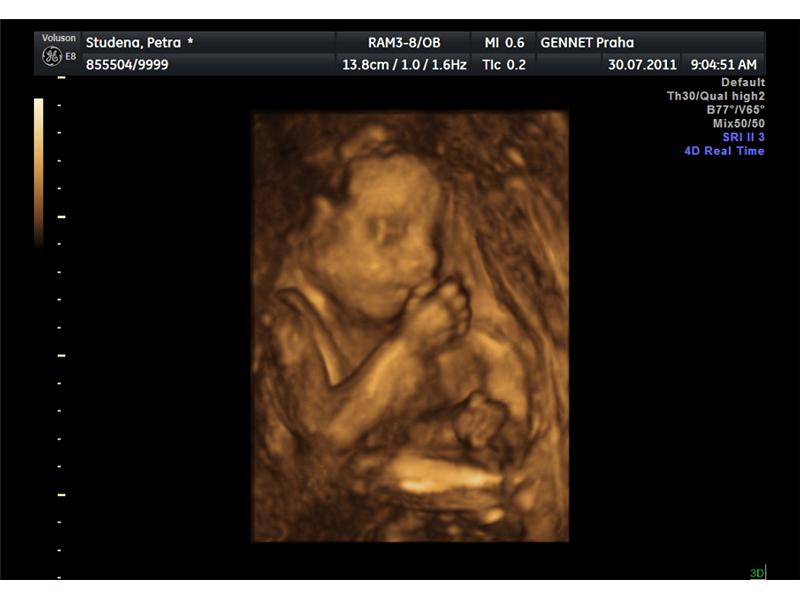

Zdroj: archiv redakce